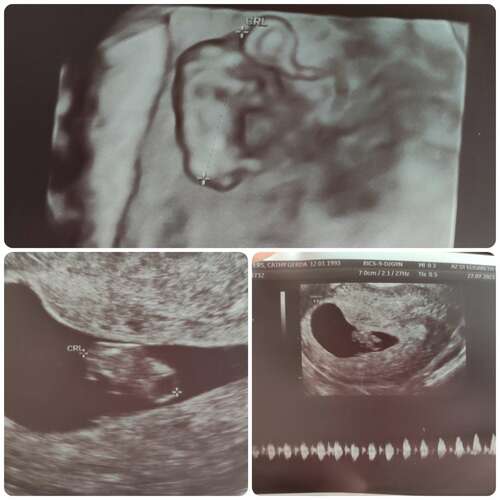

Dit was onze echo met 8+5 馃槉

Haii hier was ik 8+3 Je ziet een klein beetje de stompjes waar de armpjes komen en links zijn de billetjes 馃槂 Het is zo bijzonder en mooi om al zo鈥檔 klein hartje te zien kloppen 馃グ

8+3 :) inwendige echo. Ondertussen 9+3 volgende week vrijdag de termijn echo, kan het niet afwachten om weer even te mogen spieken!